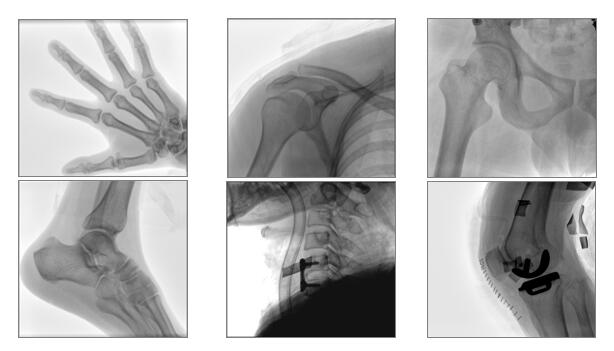

【产品临床图片】